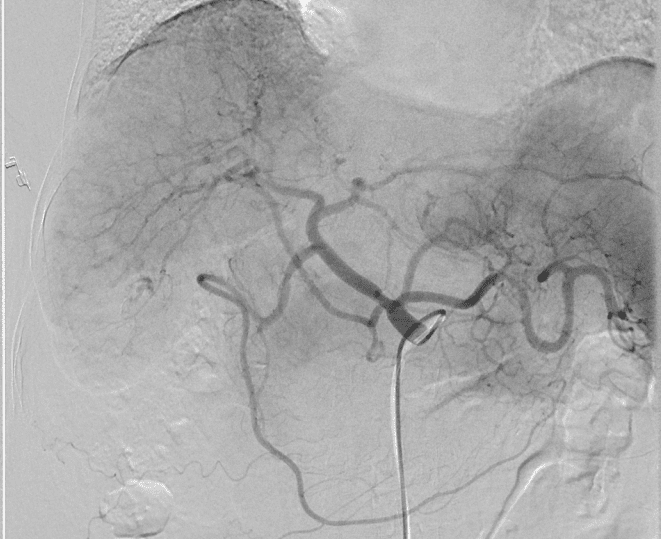

Chụp kiểm tra toàn bộ động mạch thân tạng.

Bác sĩ sẽ tạo một lối vào nhỏ trên cơ thể người bệnh để tiếp cận động mạch đùi hoặc cổ tay, sau đó luồn ống thông trong lòng động mạch, tiếp cận khối u ở gan. Dưới sự dẫn đường của hệ thống máy chụp mạch DSA, bác sĩ tiến hành bơm hỗn hợp vật liệu tắc mạch vào khối u. Hỗn hợp này gồm chất tắc mạch giúp ngắt nguồn máu nuôi dưỡng u, kết hợp với hóa chất trị liệu giúp diệt khối u.